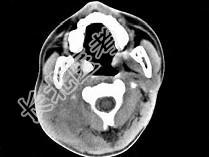

- 单项选择题男,17岁, 自诉鼻涕中带血3个月,伴耳闷、听力减退, 无发热。如图所示鼻咽部病灶最可能的诊断为 ( )

C、鼻咽癌